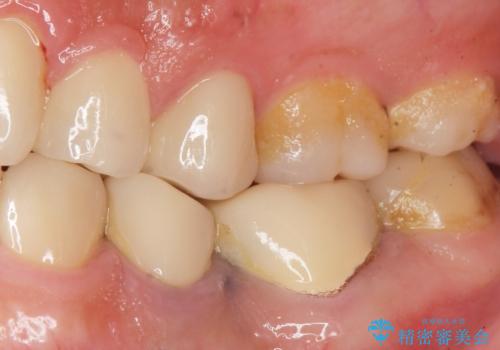

- 奥歯の被せ物をセラミックにしたいとご希望され、来院された患者様です。

左下の奥歯(左下6)の劣化した白い被せ物と金属の土台を除去し、セラミッククラウンによる補綴治療を行いました。

セラミッククラウンの天然歯のような自然な仕上がりと咬み心地に喜んで頂けました。

クラウンの種類:オールセラミッククラウン スタンダード